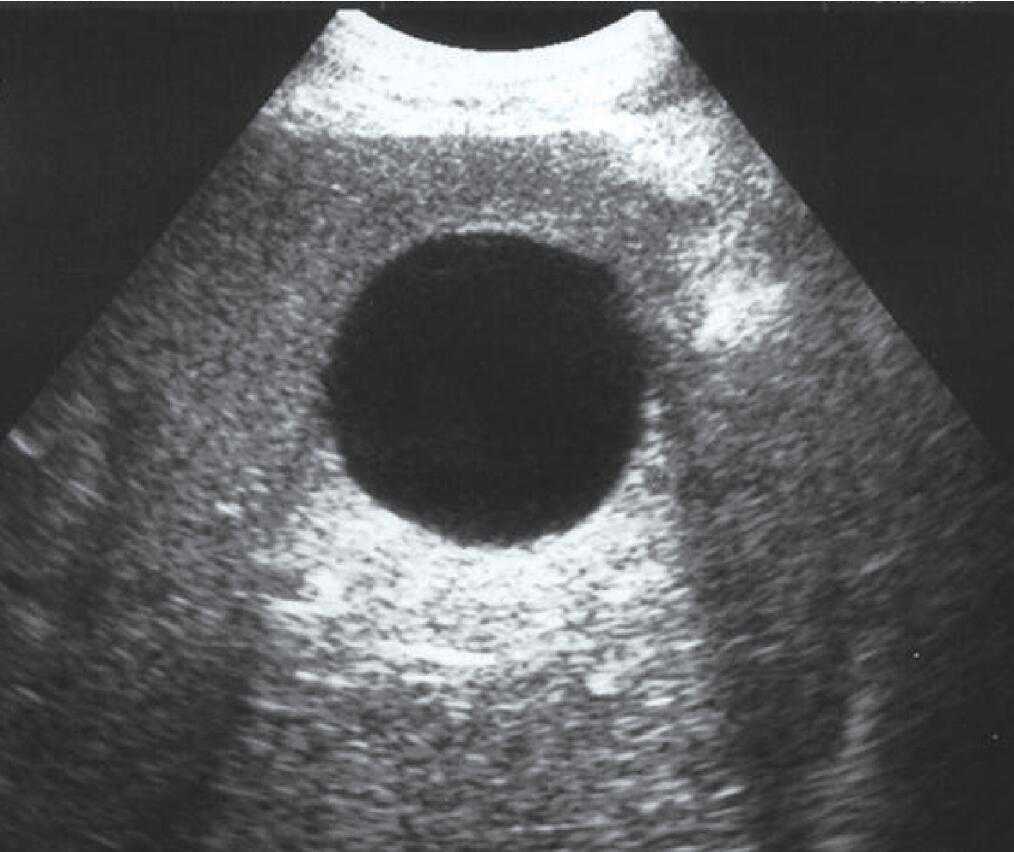

(6)声影:在超声扫描成像中,当声束遇到强反射(如含气肺)或声衰减很高的物质(如瘢痕、结石、钙化)声束完全被遮挡时,其后方出现条带状无回声区即声影,若声影内部存在混杂回声,多为气体所致;若声影内部不存在混杂回声,多为结石、钙化灶和骨骼所致(图11)。

图11胆囊结石后方声影